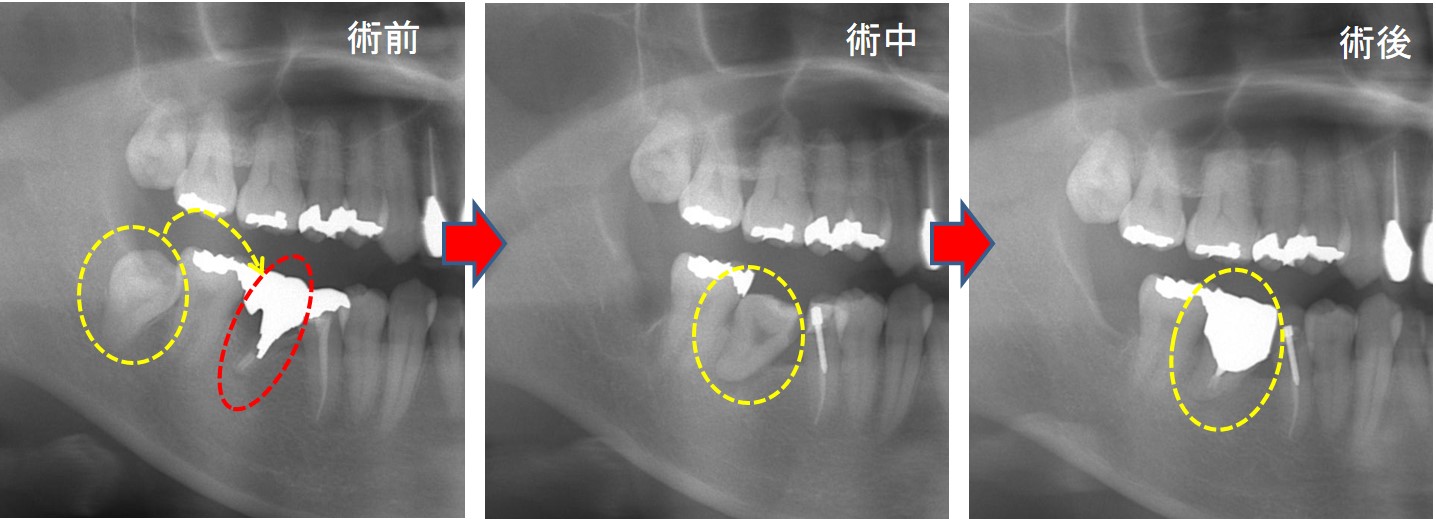

術前写真(左):赤○は虫歯で崩壊し、抜歯しなければなりません。そこで、赤○の根を抜歯して黄○の親知らず(歯茎の中に埋まっているのが見える)を移植する計画としました。

術中写真(中央):親知らずを移植した直後の写真です。糸で縫合、固定しています。

術後写真(右):4か月後、冠を装着しました。

☆レントゲン写真です。

術前→術中→術後写真です。良好に経過しています。